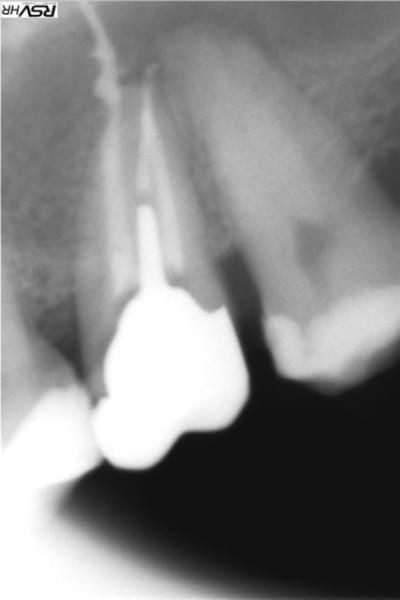

Il n'y a pas que la technique d'obturation qu'il faut revoir mais aussi l'alésage. Sur la radio, l'apex est défoncé: la racine à une courbure mésiale et l'obturation est rectiligne et perfore la racine à la courbure apicale.

La pâte est partie droite dans l'os (qui a dû être aussi alésé ...) et a fusé en nappe quand elle a atteint le sinus.

En plus c'est sur-alésé et certainement avec des instruments trop rigides qui ont tout défoncé.

ci-joint un cas de dépassement de pâte canalaire après compactage mac spadden

heureusement pour moi et le patient la pâte du sealite regular

s'est dissous naturellement de fin 2012 (dépassement)

à fin 2015 trace disparue

Je te donne mon interprétation "airylis"

tu as une 14 avec 2 racines la palatine plus longue qui donne donc l'impression d’être devant la racine vestibulaire

le cône de gutta ne suit pas la courbure donc alésage légèrement droit et faux canal et donc la pâte a fusé

et suivi la courbure de ton sinus d’où l'arc de cercle;

la membrane de schneider a sans doute empêché la pâte de fuser dans le sinus;donc pour moi pas d'effraction de la membrane sinusienne sion image verticale....

Oui la pate ne semble pas être dans le sinus mais entre la membrane et l'os , mais d'une part je mets très peu de pate et d'autre part cette image ne ressemble pas à un dépassement , c'est "canalisé" ... J'arrive maintenant à positiver car le scanner du sinus fait quelques jours apres révèle plusieurs anomalies mais ne parle pas de ma pate et le patient est content de ne plus avoir ses douleurs sinusales , mais j'ai mis plusieurs jours à retrouver le sommeil aprés ce traitement et à oser faire des endos ...

Je pense que tu as fait ce qu'on appelle un zipping de ton apex. en gros tes limes de mise en forme ont peu à peu dévier la courbure. En gros apex explosé...

Tu as sûrement fait une erreur de calibration de ton maître cône de gutta. Toujours vérifier qu'on aune bonne butée. Il semble que ton dépassement soit un mélange de gutta et de pâte, donc peu probable que cela se résorbe.

Même chose que M2, faux canal avec dépassement (ne suit pas la courbure apicale) et fusée de pâte. On le voit bien sur la radio